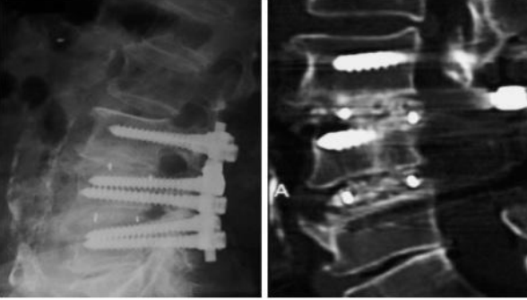

临床优势

1.良好的生物活性、结合植骨增强骨融合

2.椎间远期融合效果好,沉降率低

3.型号设计多样,满足临床需求